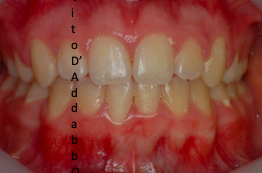

In alcune malocclusioni i denti superiori non coprono adeguatamente quelli inferiori con la presenza in alcuni casi di una beanza fra le due arcate. Questo può essere dovuto ad abitudini viziate come il succhiamento del dito, una deglutizione scorretta, una postura della lingua alterata o un problema scheletrico. In questo esempio il problema è associato ad una terza classe scheletrica.

dopo – fase 1